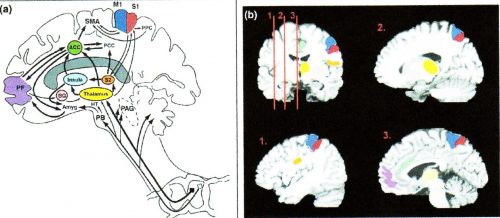

痛みを感じている時に脳が活動する部分を「痛みの関連脳領域 ペインマトリックス」と言います。

ペインマトリックスには2つの神経回路があるとされています。

感覚を伝える回路と、情動を伝える回路です。

ペインマトリックスに含まれる脳領域は、

感覚を伝える回路には、視床、第1次体性感覚野、第2次体性感覚野

情動を伝える回路には、偏桃体、視床下部、前帯状回、島、前頭前野が

主に活動するとされています。